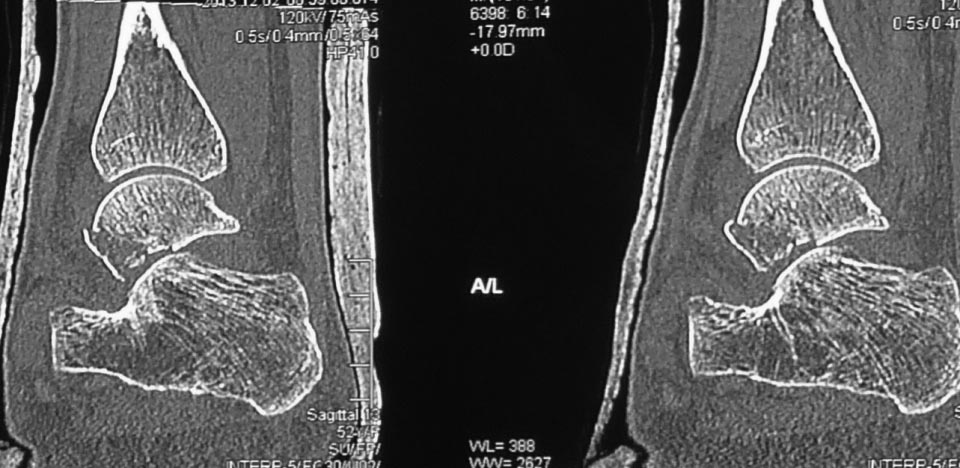

Вероятнее всего, речь изначально шла о не устраненном во время операции

вывихе проксимального фрагмента таранной кости. Во вложении похожий

случай, оперированный 10 дней назад (с послеоперационными снимками). Для

сравнения стрелками на двух рентгенограммах показан нависающий над

пяточной костью вывихнутый фрагмент таранной кости. На компьютерной

томограмме видно гораздо лучше. Так что о живом подтаранном суставе при